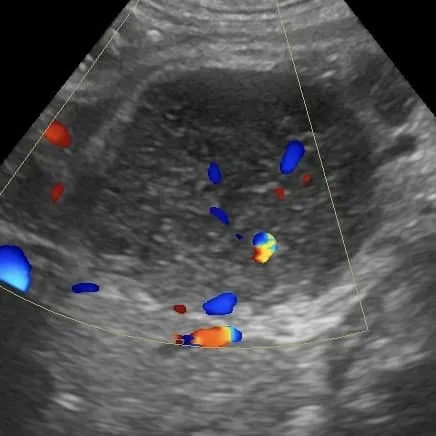

針對腫大的淋巴結、團塊,或體內病灶進行超音波導引針對腹腔腫塊或消化道壁採樣都可以確診。當然在細胞抹片的判讀上,會需要一定的經驗,且對抹片品質與採樣技巧上有一定的要求。

針對腫大的淋巴結、團塊,或體內病灶進行超音波導引針對腹腔腫塊或消化道壁採樣都可以確診。當然在細胞抹片的判讀上,會需要一定的經驗,且對抹片品質與採樣技巧上有一定的要求。